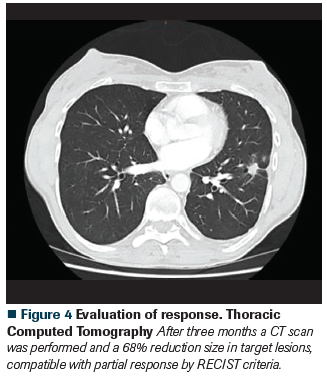

Figure 4 Evaluation of response. Thoracic Computed Tomography

The patient started treatment with osimertinib 80 mg per day. After 2 weeks of treatment, a significant improvement of symptoms was achieved with good treatment tolerability.

At the last follow-up, the patient continues with a good functional status and is tolerating the treatment properly with a PFS of 17 months.